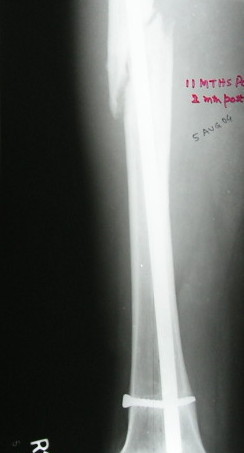

Failure to close 4/4 cortices 6 months post-op definitely meets definition criteria of non-union. Obviously, fixation has failed in this case and needs to be achieved via exchange nail.

Tough to tell from these x-rays, but fx ends appear sclerotic with bridging callus partially present - likely hypertrophic non-union, but you can do a bone scan to confirm viability.

It is agreed by almost all that this is a hypertrophic nonunion.

Ajit >>Also, there is insufficient callus to suggest a hypertrophic nonunion after 14 mths. As

Ajit >>mentioned by you the first surgeon has already opened the fracture site and probably

Ajit >>devitalised/ stripped the femur of its perisoteum. Adding bone grafts will surely help.

VMI- OK It is not hypertrophic but normotrophic nonunion. Mangal has already said so. Though the first surgeon has devitalised the femur, that was 14 mths ago. By the way, the second surgery (may be the same surgeon) 5 months ago may also have done some harm. Anyway there is no need to do bone grafting if everything is done closed.